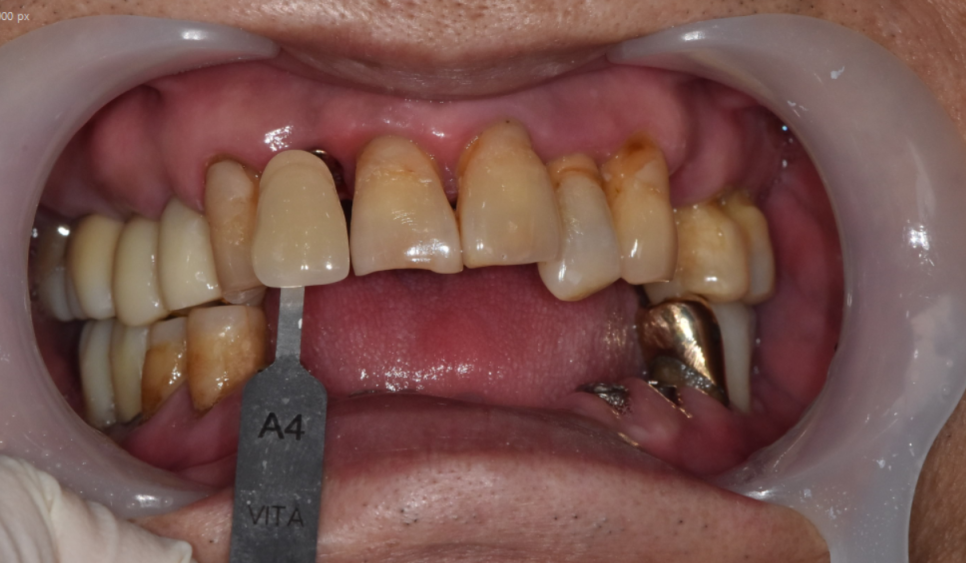

구강 내 사진을 보시면

전반적으로 치아가 길어보이죠~?

주황색 라인까지 잇몸이 덮여 있어야하는데

잇몸뼈가 내려가면서

치아도 길어져 보이는거죠~

치아 뿌리 부분만 붙잡고 있으니

위아래 치아 흔들림과 함께

통증이 있었습니다.

치료 부위 중 앞니가 포함되어 있었는데

무엇보다 중요한 것은 "심미"입니다.

색깔을 자연치와 비슷하게 하여

티가 나지 않도록 제작해드렸습니다.